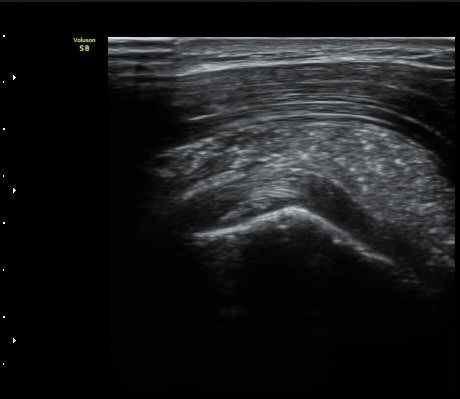

ÁÖ»ç ÈíÀΰú Á¡¾×³¶³» ÁÖ»çÄ¡·á(÷ºÎ ÆÄÀÏ) 1ÀÏ ÈÄ ½ÃÇàÇÑ °Ë»ç¿¡¼­ Á¡¾×³¶ÀÇ ºÎÁ¾ ¹× ¼®È¸ÀÇ

Á¦°Å°¡ °üÂû µÊ(±×¸² 6, 7).

ÃÊÀ½ÆÄ°Ë»ç¸¦ ÀÌ¿ëÇÑ Á¤È®ÇÑ Áø´Ü°ú ÀûÀýÇÑ Ä¡·á´Â Ç×»ó ÁÁÀº °á°ú¸¦ º¸ÀÓ.